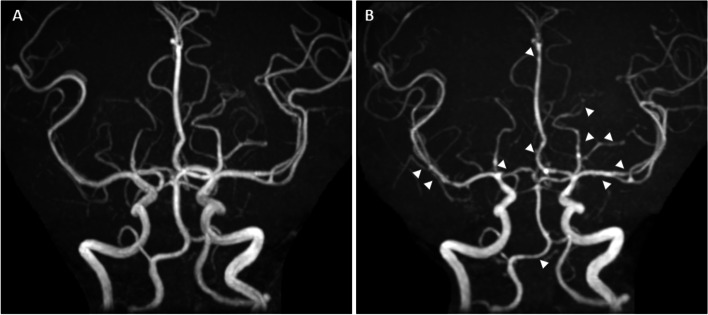

Five days after onset, brain MRI showed regions of hyperintensity in the right frontal lobe, bilateral parietal cortex and subcortex, and bilateral cerebellar lobes on FLAIR images (Fig. 1A). In addition, although the apparent diffusion coefficient (ADC) map showed elevations (Fig. 1B), no region of hyperintensity was observed on the diffusion-weighted image (DWI), suggesting angioedema (Fig. 1C). No abnormal findings were observed on brain magnetic resonance angiography (MRA) at the time of onset of the first headache (Fig. 2A). However, four days after the onset, multiple cerebrovascular spasms were observed, in which alternate contractions and dilations of several main arteries occurred (Fig. 2B). On the electrocardiogram (ECG) five days after the onset of the first headache, ST depression was observed in limb leads II, III, and aVF, and in the chest leads V3 to V6 (Fig. 3A). Ultrasound cardiography (UCG) showed a hypokinesis at the base of the side of intraventricular septum, with a slight decrease in ejection fraction (EF = 51.6%) and in fractional shortening (FS = 25.9%) (Fig. 4A). Although no symptoms of angina were observed 5 days after onset of first headache, left ventricular hypofunction leading to impending heart failure was suspected. Therefore, a calcium channel blocker and a nitrate were administered.

Based on her clinical course and imaging findings, she was diagnosed with reversible cerebral vasoconstriction syndrome (RCVS) with cardiac involvement. We administered 5 mg of the calcium channel blocker amlodipine besylate, 25 mg of nitroglycerin, and 500 mg of the antiepileptic drug levetiracetam. The hyperintense regions on FLAIR images completely disappeared 23 days after onset of first headache. She showed no exacerbation of heart failure, and the ECG (Fig. 3B) and UCG (Fig. 4B) findings were found to be normal eight days after onset of first headache. To avoid the risk of vascular spasm by iodinated contrast medium, we did not perform cardiac catheterization or coronary computed tomography (CT)-angiography until her RCVS was fully controlled. Since no recurrence of symptoms was observed after the treatment, we performed coronary CT-angiography seven months after the onset, which showed no significant vasoconstriction in any coronary artery (Fig. 5A, B).